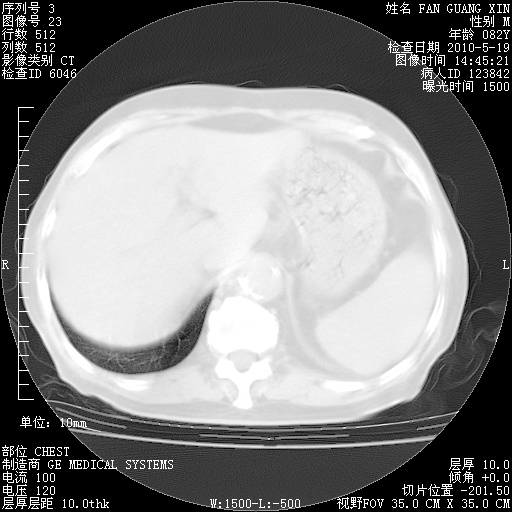

复查肺部CT,明显好转。为什么发热呢?

治疗3周后的肺部CT

治疗3周后的肺部CT纵隔窗